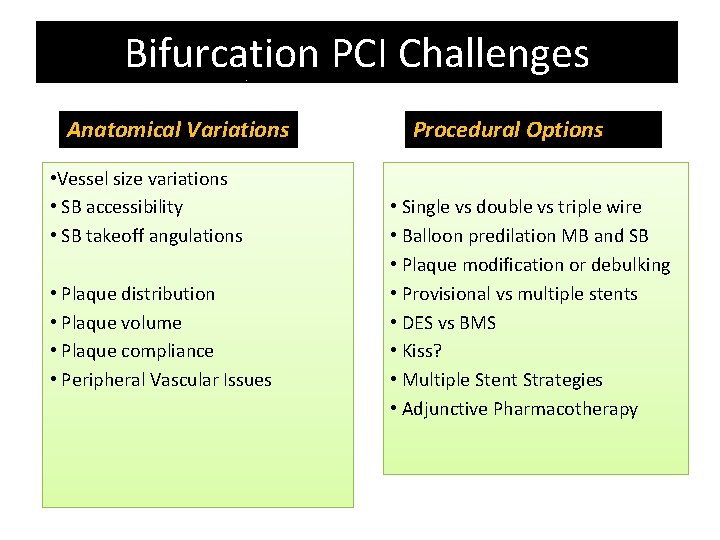

Bifurcation PCI Challenges Anatomical Variations • Vessel size variations • SB accessibility • SB takeoff angulations • Plaque distribution • Plaque volume • Plaque compliance • Peripheral Vascular Issues Procedural Options • Single vs double vs triple wire • Balloon predilation MB and SB • Plaque modification or debulking • Provisional vs multiple stents • DES vs BMS • Kiss? • Multiple Stent Strategies • Adjunctive Pharmacotherapy